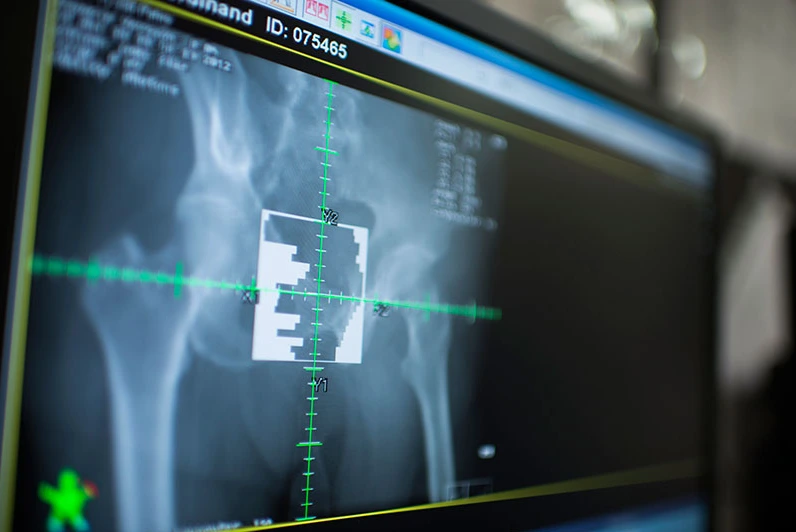

치료 조정설에는 여러 콘솔, 모니터, 오디오 시스템 등이 즐비하게 놓여 있어. 복잡할 거야. 처음에는 신기할 거야. 근데, 그런 거 신경 쓰지 말고 환자 치료하는 모니터를 주의 깊게 봐. 여기서 잠깐!!! 뭔가 기억나지 않아? <CCTV=REV>

아직도 모른다면 정말 실망이야. 그래. 이해한다고 치자. 그럼, <BEV>는? 아직도 모른다면 빨리 찾아봐. 기다려 줄 테니. 책에서 모의치료 혹은 치료계획 부분을 찾아봐.